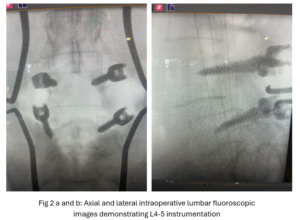

This 54-year-old female with a long history of low back pain presents with three weeks of a progressive right footdrop with associated numbness and tingling of the right leg. In addition, she had right lateral hip pain down to the dorsum of her foot. She first noticed her right foot slapping the floor when she walked. She had no prior trauma or unusual activity before this began. Her chiropractor, who had treated her back pain for a long time, first noticed the foot drop and referred her for further evaluation. She presented with ⅖ strength in her right dorsiflexor. MRI revealed a large right L4-5 foraminal synovial cyst with some mass-effect on the thecal sac. (Fig. 1) She also had an associated grade 1 spondylolisthesis. Because the cyst was more foraminally-oriented, it had the majority of its effect on the right L4 nerve root. It was felt the patient required surgery to attempt to reverse her weakness. We performed a decompressive laminectomy at L4, removing the inferior facet process on the right in order to gain lateral and foraminal access to the right L4 nerve root. In the lateral recess there was a heap of inflammatory tissue which we entered, revealing the cyst. The medial wall was stuck to the dura. We internally decompressed the cyst which was mainly gelatinous material with some fluid. We dissected and removed as much of the cyst we could safely remove but left the medial wall for fear of removing it would cause a CSF leak, upon removing the bulk of the cyst we encountered anteriorly the descending and exiting right L4 nerve root which was purplish in color and clearly inflamed. We performed a generous foraminotomy of the right L4 as well as the right L5 nerve root. We also performed an instrumented fusion at L4-5 (Fig. 2).